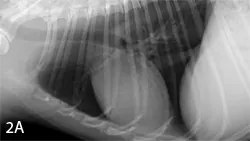

Expiratory (A) and inspiratory (B) right lateral radiographs from a 7-year-old neutered male poodle. Because the act of respiration changes the thoracic appearance, inspiratory films should be attempted to distinguish artifacts from true lung pathology.